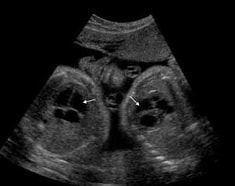

「一絨毛膜性双胎」と「二絨毛膜性双胎」

つまり、お互い別々のお膳を持っているので、自分の取り分は確保されています。ところが、一絨毛膜性双胎の場合は、ひとつのお膳を2人で分け合うことになるので、どちらかが相手の分まで奪い取ってしまうこともあり得ます。このため、一絨毛膜性双胎は、二絨毛膜性双胎よりも注意が必要で、健診の回数も多くなります。